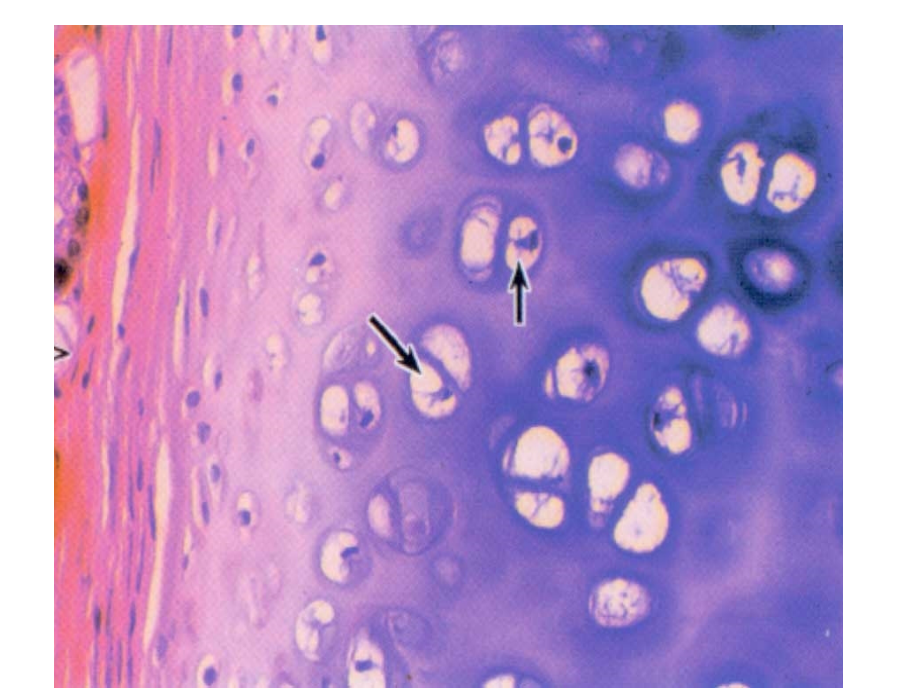

单击此处编辑母版标题样式,单击此处编辑母版文本样式,第二级,第三级,第四级,第五级,*,1.2.3.,单核细胞,4.5.6.,淋巴细胞,7.8.9.10.11.,中性粒细胞,12.13.14.,嗜酸性粒细胞,15.16.,嗜碱性粒细胞,17.,红细胞,18.,血小板,同源细胞群,在软骨中部可见到由,26,个细胞组成的,群落,,它们由同一个幼稚的软骨细胞分裂增殖而来,称为,同源细胞群,。,中央管,穿通管,骨小管,Muscle tissue,第七章 肌组织,肌组织,肌细胞,(,肌纤维,),细胞膜,肌膜,细胞质,肌质,滑面内质网,肌质网,细胞间质:结缔组织、血管、,神经,起源:胚胎时期,间充质,发育而来,骨骼肌,心肌,不随意肌,随意肌,分类:,肌组织,横纹肌,平滑肌,第一节、骨骼肌,(skeletal muscle),(一)肌纤维光镜结构,细胞长圆柱状(,1-40mm,);,10-100um,核多(几十到几百不等),在细胞边缘,肌膜下方,;,胞质,嗜酸性,,,含大量与细胞长轴平行的,肌原纤维,,,有,周期横纹,。,模式图,纵切面,横切面,肌原纤维,:,细丝状,其表面有明暗相间的带交替排列,分别称,明带,和,暗带,,同一骨骼肌纤维中所有肌原纤维的明带和暗带都排在,同一平面,上,构成肌纤维表面的,周期横纹,。,2.,骨骼肌,纵断,明,带,暗,带,肌,原,纤,维,I,I,A,A,带,I,带,I,带,肌 节,暗,(A),带,明,(I),带,H,带,M,带(线),Z,线,I,I,1 A,+,+,肌节:,相邻两,Z,线之间的一段肌原纤维:,1/2I,+,A,+,1/2I,。,其长度随着肌纤维的收缩和舒张而变化。,肌原纤维结构和功能的,基本单位,。,I,带:由细肌丝组成,H,带:由粗肌丝组成,A,带:由粗肌丝和细肌丝组成,肌原纤维,:由粗、细肌丝构成,沿肌原纤维长轴排列,I,带:由,细肌丝,组成;,H,带:由,粗肌丝,组成,A,带:由,粗肌丝,和,细肌丝,组成。,A,带,I,带,I,带,M,线,Z,线,舒张,收缩,骨骼肌收缩时肌节变化:,细肌丝沿粗肌丝向,A,带内滑动,A,带不变,I,带缩短,H,带缩短或消失,肌节缩短,骨骼肌舒张时肌节变化:,细肌丝脱离粗肌丝退回原处,I,带变宽,H,带变宽,肌节变长,结构:,在肌纤维横断面同一,水平上,,肌膜,从多点,向肌质凹陷形成,小管,分布:,人和哺乳动物在明,暗带,交界处,。,功能:,将肌膜的兴奋迅速同,步地传至肌纤维内部,横小管:,T,小管,(二)肌纤维电镜结构,肌质网,组成:是肌纤维内高度发达的,滑面内质网,,肌质网纵行并包绕每条肌原纤维,又称,纵小管,(,L,小管,)。,终池,:位于横小管两侧的肌质网扩大呈,扁囊,,称终池,将兴奋传至肌质网膜。,三联体,=1,根横小管,+,两侧的终池,功能:钙库,浓缩、储存和释放,Ca+,肌丝滑行学说,运动终板,肌膜,T,小管,L,小管,释放,Ca,2,激活肌钙蛋白,肌动蛋白位点暴露,与肌球蛋白结合,细肌丝滑动,肌原纤维、肌纤维、肌肉收缩,ATP,二、心肌,(cardiac muscle),LM,:不规则短圆柱形,连接处有,闰盘,;,核,1-2,个,卵圆形,位于,细胞中央,;胞质丰富,含线粒体、糖原脂滴等,有,横纹,,但不如骨骼肌明显。心肌纤维间有丰富毛细血管。,心肌细胞无再生能力,2.,EM,:,与骨骼肌相比,有以下特点,:,(,1,)肌原纤维少,粗细不均,(,2,)横小管粗,少,,位于,Z,线水平,(,3,)纵小管不发达,常形成,二联体,(,4,)有,闰盘,(intercalated disc),,位,于,Z,线水平,呈阶梯状,横向部分,有,中间连接和桥粒,,起连接作用;,纵向部分有,缝隙连接,,起传导电信,号作用。,(,5,),富含线粒体,,长且粗,分布于肌丝,束之间,纵行排列。,闰盘,线粒体,闰盘,(intercalated disc),三、平滑肌,(smooth muscle),LM,:,细胞梭形;,单核,,,核杆状或椭圆形。,位于细胞中央;,胞质,嗜酸性,。,平滑肌,(横切和纵切),三种肌,纤维的,光镜结构,特点,。,骨骼肌和心肌纤维的,超微结构,。,3.,肌节,、横小管、三联体的概念,。,4.,闰盘,的结构和功能,。,肌组织的知识点,:,肌纤维超微结构与肌收缩,;,钙与肌收缩,课后了解及延伸:,